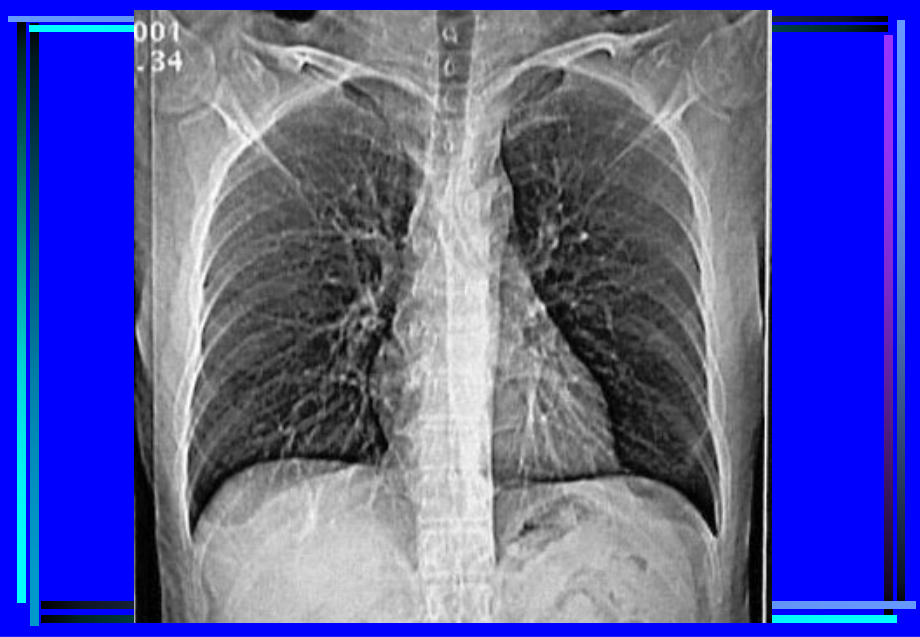

,单击此处编辑母版标题样式,单击此处编辑母版文本样式,第二级,第三级,第四级,第五级,*,胸部CT诊疗大量实例CT片,(二)增强扫描,(contrast enhancement,CE),1.注药方法,团注法 (bolus injection),静滴法,2.扫描程序,静态CT扫描,动态CT扫描(dynamic CT scan),(三)特殊扫描,1.薄层扫描,2.高分辨率CT扫描,(High resolution CT,HRCT),3.CT血管造影,(CT angiography,CTA),4.心电门控扫描,二、CT对胸部疾病的诊断价值与限度,(一)诊断价值,1.肺部小病灶与早期病变,2.咯血查因,3.肺不张、肺实变,4.肺肿瘤分期,5.肺弥漫性病变,6.肺气肿的诊断及功能评价,7.肺血管性病变,8.胸水查因,(二)影响CT检出与诊断的因素,(主要为常规CT),1.运动伪影,2.部分容积效应,3.层厚与层间距,4.大量胸水,5.一病多像,一像多病,三、胸部正常CT解剖,(一)窗技术,1.纵隔窗:,窗位3060Hu,窗宽300500Hu,2.肺窗:,窗位-700-400Hu,窗宽10001500Hu,(二)纵隔(mediastinum),(三)肺(lung),第二节 肺部疾病的CT诊断,一、先天性疾病,1.肺隔离症(pulmonary sequestration),某一肺段和正常肺组织及气管和支,气管树相互分离,无呼吸功能,血供来,自主动脉系统,分叶内型和叶外型两类。,CT表现:,部位:两下肺、脊柱旁。,形态:囊实性或囊性或实性,邻近肺,野斑片状影。,血供:体循环,病灶内血管异常。,鉴别诊断:,支气管源性囊肿、肺脓肿、先天性膈疝。,2.支气管囊肿(bronchogenic cyst),为支气管的先天发育异常,根据组,织学来源可分为支气管囊肿和支气管肺,囊肿(pulmonary bronchogenic cyst)。,CT表现:,部位:纵隔与肺的任何部位,多见于,气 管隆突5,cm,范围内。,形态:圆形、椭圆形、边缘锐利,壁,菲薄。,密度:均匀,可有出血和液气平,壁,可强化。,二、支气管扩张症(bronchiectasis),病因:先天性或后天性,病理:肉眼观,支气管呈柱状、囊状、静,脉曲张状或混合状扩张。,镜下观,粘膜柱状上皮呈急、慢性,炎性改变,伴弹力纤维、,平滑肌和软骨的损害。,CT表现:,病变支气管壁增厚,管腔,扩大,形态多样。,1.柱状扩张:“双轨”征、“印戒”征。,2.囊状扩张:葡萄串状、卷发样。,3.曲张形扩张:粗细不均的囊柱状。,4.混合型,合并粘液栓时,腔内可见棒状,或结节状软组织密度影,咳痰后可,消失,同时可见肺野内出血,继发,感染等征象。,三、肺感染性病变,1.支气管肺炎,支气管肺炎(bronchopneumonia),或小叶性肺炎(lobular pneumonia),病 理:,小支气管壁充血、水肿、间,质炎性细胞浸润,小叶渗出、,实变、气肿或不张。,CT表现:,两肺中下野中内带,支气管,血管束增粗,沿其分布小斑,片影及边缘模糊的小结节影。,2.大叶性肺炎,大叶性肺炎(lobar pneumonia),,炎症累及整个肺叶,或呈肺段分布。,病理:充血期,,毛细血管充血,肺,泡内可有少量浆液性渗出。,红色肝样变期,,渗出液中含,较多红细胞。,灰色肝样变期,,渗出液中含,大量白细胞。,消散期,,渗出液溶解、吸收。,CT表现:,渗出期表现为磨玻璃样影;实变,期呈叶、段的实变,可见空气支气管,征,叶间裂可向外膨出;消散期则呈,斑片状影。,鉴别诊断:,阻塞性肺炎,结核性大叶炎、,肺肿瘤(腺癌、肺泡癌或淋巴瘤)。,3.肺脓肿,肺脓肿(lung abscess),由化,脓性细菌引起的肺坏死性炎性病变,,分急性和慢性肺脓肿。,病理:,细支气管阻塞,小血管炎性栓塞,,肺组织坏死、液化,周围有纤维,组织增生。,CT表现:,急性期:大片密实影,中心密度较,低,空洞形成后,壁厚而模糊,内有液,平;慢性期:洞壁清晰,内壁多不规整,,增强扫描洞壁强化,支气管、肺血管于,脓肿边缘截断。,鉴别诊断:,结核空洞、癌性空洞,4.肺结核,肺结核(pulmonary tuberculosis),由人型或牛型结核杆菌引起的肺部慢性传,染病。,病理:,渗出结核性肺泡炎,增殖,结核性结节肉芽肿。继发改变:干酪样坏,死、液化、空洞、播散;纤维化、钙化。,CT表现:,型:原发性肺结核,(primary tuberculosis),纵隔、肺门淋巴结增大,增强扫描,多呈环形强化。肺内原发灶呈片影或段、,叶的实变,内可见低密度坏死、空洞。,可合并叶或段的不张。,型:血行播散型肺结核,(acute miliary tuberculosis and chronic,disseminated tuberculosis),急性血行播散型,CT表现为双肺广泛,分布的12mm小点状阴影,密度均匀,边界,清,分布均匀,与支气管走行无关,以HRCT,显示为佳。亚急性或慢性血行播散型,病灶,大小不一,密度不均,可有钙化,上中肺野分,布为主。,型:继发性肺结核,(secondary pulmonary tuberculosis),肺尖后段、下叶背段常见,单发或多,发腺泡结节状影,小叶、肺段或肺叶,实变。,病变密度不均,可见钙化、坏死、空,洞,纤维索条影。,病灶邻近胸膜增厚。,caseous pneumonia:,大叶性实变,可见空气支气管征,,小空洞,下肺野可见支气管播散灶。,tuberculoma:,类圆形结节,可呈浅分叶,边缘,清晰,直径24,cm,,内可有坏死,结,节状、斑点状或层状钙化,周边常见,卫星灶,增强扫描结节多呈环形强化。,型:胸膜炎型(结核性胸膜炎),可单独或与肺部结核合并存在,,表现为胸水,胸膜增厚或胸膜结节。,肺结核的鉴别诊断:,其它感染 肺癌 炎性假瘤 肉芽肿,肺癌,原发性支气管肺癌,(primary bronchogenic carcinoma),是呼吸系统常见病,在全身恶性肿瘤,中居第二位。,病理:,肺癌起源于支气管上皮,腺体或细,支气管肺泡上皮。,组织学分型:,小细胞肺癌和非小细胞肺癌,(鳞癌、腺癌、大细胞未分化,癌、复合癌)。,按发生部位分:,中心型、外围型、细支气,管肺泡癌。,CT表现:,(1)中心型肺癌:,肺门肿块,常伴肺不张或阻塞性肺炎,支气管异常,淋巴结转移及血行转移,纵隔侵犯,左上肺非特异性炎症,(2)周围型肺癌,肺外周结节,多呈分叶状,可有细短,毛刺。,结节密度多不均匀,可有空泡征,支,气管气象,坏死、空洞、少数有钙化。,血管纠集、细支气管截断。,胸膜牵引征,增强扫描,,CT,值增加多在20,Hu,以上。,转移征象,(3)细支气管肺泡癌,结节型:同周围型肺癌,弥漫型:双肺弥漫分布的腺胞结,节,可融合。,实变型(肺炎型):肺段或叶的,实变,常合并腺泡结节。,(4)几种特殊类型的肺癌:,肺上沟癌(Superior sulcus carcinoma,Pancoast tumor),纵隔型肺癌,肺炎型肺癌,重复癌,第三节 纵隔疾病的CT诊断,一、胸内甲状腺,(intrathoracic thyroid gland),病因:,甲状腺肿、腺瘤、囊肿、癌,CT表现:,位置:,前上纵隔,气管和胸骨间,可,推压气管,上与甲状腺相连。,密度:,较高、常有囊变、钙化、强化,明显。,二、胸腺增生与胸腺瘤,(一)正常胸腺,位于前上纵隔,主动脉弓前,,呈三角形,新月形或箭头状,20岁以,后逐渐委缩,为脂肪替代。,正常胸腺大小;1月14岁厚,度22mm;厚度与主动脉弓直径之比:,1岁以内1.8,16岁1.2,614岁,0.9。,(二)胸腺增生,(thymic hyperplasia),弥漫性增生,结节状增生,(三)胸腺瘤(thymoma),病 理:,上皮细胞为主型、淋巴细胞为主型,和混合型。,CT表现:,分非侵袭性和侵袭性胸腺瘤。前上,纵隔内结节影,向一侧或两侧突出,,边界清晰密度较均匀,可有囊变和,钙化,增强扫描明显强化。侵袭性,者弥漫浸润于大血管间,心包和胸,腔积液。,鉴别诊断:,胸腺增生与胸腺瘤 畸胎瘤 淋巴瘤,三、畸胎瘤(teratoma),病理:,来源于原始生殖细胞,一种或多,种胚胎成分,有囊性和实质性,CT表现:,前纵隔,边缘光滑之厚壁囊性肿块,,含脂肪、脂液分层、钙化、骨骼或牙齿、,囊性畸胎瘤壁常呈蛋壳状钙化。,四、淋巴瘤(lymphoma),病理:,淋巴结或结外淋巴组织,分,Hodgkin disease,HD和non,Hodgkin lymphoma,NHL,CT表现:,纵隔肺门多组淋巴结肿大,可,融合成团,压迫或侵犯纵隔结构。,偶有坏死与钙化,强化程度较低。,鉴别诊断:,淋巴结结核 结节病,胸腺瘤 转移瘤,五、心包囊肿(pericardial cyst),多为单房,可发生于心包的任何,部位,以心膈区多见。常位于右心,膈角区,呈边缘清晰锐利的囊状影。,鉴别诊断:,心包憩室 支气管囊肿,六、神经源性肿瘤,(neurogenic tumor),是后纵隔最常见的肿瘤,多起源于肋,间神经内侧段或椎旁交感神经链。分神经,纤维瘤、神经鞘瘤、神经节细胞瘤、神经,母细胞瘤等。,CT表现:,后纵隔脊柱旁类圆形肿块,密度均匀,,部分呈哑铃状,椎间孔扩大,肋骨头和脊,椎受压,良性者边缘锐利,恶性者边缘不,清,侵蚀骨骼,增强扫描呈中等强化。,The end,谢 谢!,